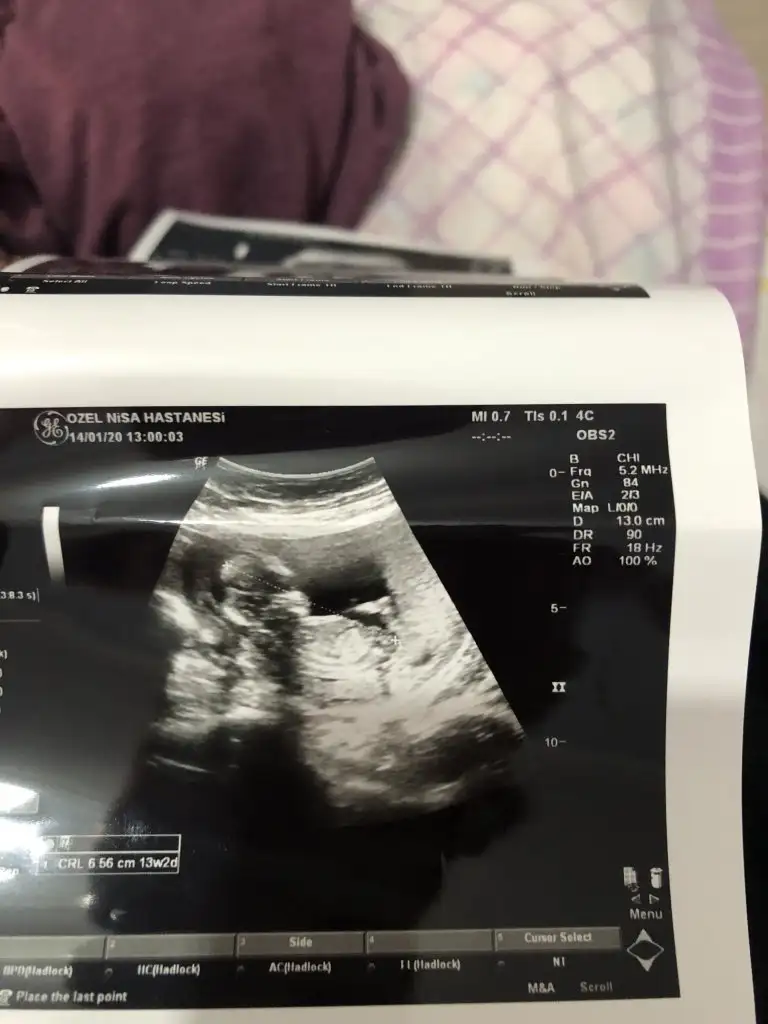

Tam net degil sanki erkek gibi ama eminde degilim başka usg varsa paylaşın 11 de olabilirCinsiyet tahmini yapabilirmisiniz?12. haftadayız.

Bunlarda 10+6 haftalıkken11 haftasınıda paylaşırmısınız sanki erkek gibi gibi